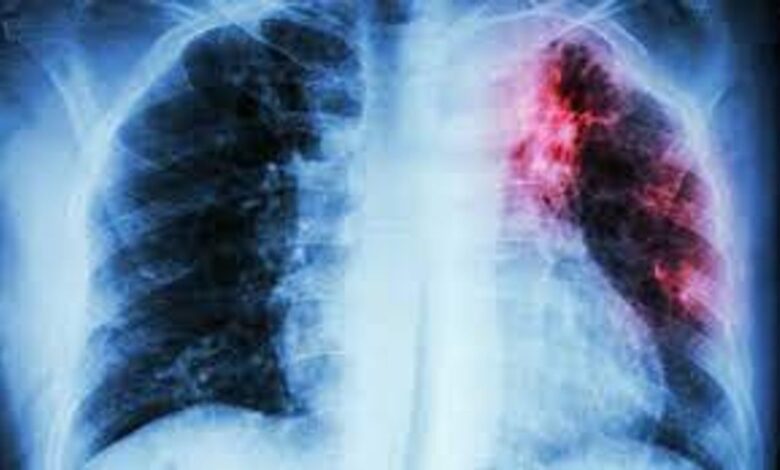

नई दिल्ली, 19 नवंबर: विश्व स्वास्थ्य संगठन (WHO) ने भारत में तपेदिक (टीबी) उन्मूलन के प्रयासों को ‘उत्साहजनक प्रगति’ बताते हुए देश की सराहना की है। डब्ल्यूएचओ दक्षिण-पूर्व एशिया क्षेत्रीय कार्यालय ने मंगलवार को जारी अपने आधिकारिक बयान में कहा कि भारत ने हाल के वर्षों में टीबी नियंत्रण और मौतों में कमी के मोर्चे पर उल्लेखनीय सुधार दिखाए हैं।

डब्ल्यूएचओ की ओर से जारी बयान में कहा गया कि भारत में टीबी से संबंधित मृत्यु दर में सुधार के स्पष्ट संकेत मिले हैं। संगठन ने माना कि भारत द्वारा बीमारी की रोकथाम, निदान और उपचार को तेज करने के लिए किए जा रहे व्यापक प्रयासों का असर अब जमीनी स्तर पर दिखाई देने लगा है।

टीबी उन्मूलन के वैश्विक अभियान में भारत की भूमिका सबसे महत्वपूर्ण मानी जाती है, क्योंकि विश्व के कुल टीबी बोझ का बड़ा हिस्सा दक्षिण-पूर्व एशिया क्षेत्र में है और इसमें भारत की भागीदारी निर्णायक है।